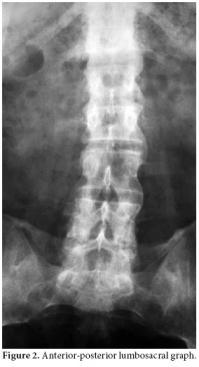

A 48-year-old male patient who had been followed up in another center with the diagnosis of AS was referred to our clinic with complaints of pain in the lower back, neck, and right hip increasing at rest and decreasing with activity. The locomotor system examination revealed that the cervical and lumbar vertebra motions were limited and painful. The motions of the right hip were painful, and extension and rotation were limited. The Mennel test and Patrick-Faber test were positive on the right side. The lumbar Schober test was 2 cm, and chest expansion was 2 cm. The anterior-posterior sacroiliac joint graph revealed bilateral stage IV sacroiliitis along with concentric narrowing in the joint space of the right hip (Figure 1), and the anterior-posterior lumbosacral graph revealed syndesmophytes (Figure 2). The patient was found to be human leukocyte antigen-B (HLA B27)(–). He had been followed up for seven years at another center with the diagnosis of renal failure associated with nephrolithiasis and had used sulfasalazine and leflunomide for AS. The patient had stopped using sulfasalazine and leflunomide on the recommendation of the nephrology department 1.5 months before attending our clinic. The patient was hospitalized for adjustment of his medical treatment. During follow-up, his temperature was 38-38.5 °C, and the patient developed abdominal pain. Detailed history revealed that the patient had been suffering recurrent attacks of fever and abdominal pain once a month for 15 years. At the time of the attack, the laboratory findings were as follows: Erythrocyte sedimentation rate (ESR): 74 mm/h, C-reactive protein (CRP): (++++), fibrinogen: 721.2 mg/dl (180-360 mg/dl), serum creatine: 1.6 mg/dl (0.5-1.2 mg/dl), blood urea nitrogen: 66 mg/dl (10-50 mg/dl), creatine clearance: 42 ml/min (71-151 ml/min), and microprotein in 24-hour urine: 333 mg/day (<150 mg/day). The patient had combined heterozygote M680I and M694V mutations of the MEFV gene which is common in FMF. There was no finding of hepatosplenomegaly on the abdominal ultrasonography. The gingival biopsy was negative for amiloidosis. The patient's daughter, who had similar attacks, was also diagnosed with FMF eight months after him. The patient was started on colchicine treatment (1.5 mg/day), and in the follow-up, he had attacks of abdominal pain and fever. His joint-related complaints regressed but did not completely resolve. The patient had been on leflunomid for 1.5 years and sulfasalazin for six months with no benefits and suffered from chronic renal failure. Thus, a TNF-α inhibitor (Adalimumab, 40 mg every other week) was added to the treatment regimen with colchicine after two months. After the patient used this combination for nearly one year, his complaints significantly improved. The patient had only one attack in that period. However, the patient's adherence to therapy was poor, and he did not use the TNF-α inhibitor for four months. He reapplied to our clinic with the complaint of increased joint pain. He reported one abdominal pain attack during these four months. The Bath Ankylosing Spondylitis Disease Activity Index (BASDAI) and laboratory findings of the patient before, during, and after dropping out of the treatment have been presented in Table 1. After the controls, the patient was restarted on TNF-α inhibitor (Adalimumab) treatment.

Familial Mediterranean fever is a disease usually seen among people with Mediterranean origin and is characterized with self-limited attacks of fever and polyserositis.[2] Articular involvement is the second most common presentation following abdominal pain.[13] One of the musculoskeletal involvement forms of FMF is spondyloarthropathy, and, almost always, HLA-B27 is negative. In these patients, generally minimal radiological spinal involvement is accompanied with unilateral or bilateral sacroiliitis, recurrent entesitis, and inflammatory low back and neck pain.[5] It has also been reported that AS may accompany FMF.[5,8,14] In our patient, a positive Schober's test, limited chest expansion, and the presence of bilateral stage IV sacroiliitis on the anterior-posterior sacroiliac joint graph with syndesmophytes on the anterior-posterior lumbosacral graph suggested FMF accompanied by AS.